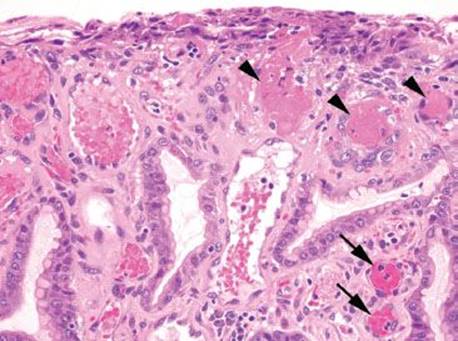

Figure 2.218 GAVE. This spectacular example of GAVE shows a number of intravascular thrombi (arrowheads). Note, fibrin is hot-pink with a homogenous appearance. In contrast, the nearby congested vessels are engorged with red blood cells (not thrombi) and appear a bolder shade of red (arrows).